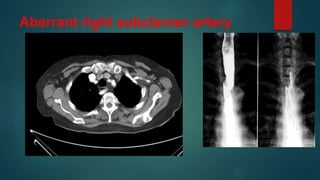

Aberrant right subclavian artery

• #9 Aberrant right subclavian arteries (ARSA), also known as arteria lusoria, are one of the commonest of the aortic arch anomalies.  Instead of being the first branch (with the right common carotid as the brachiocephalic artery), it arises on its own as the fourth branch, distal to the left subclavian artery. It then hooks back to reach the right side with its relationship to the oesophagus variable: 80% posterior to the oesophagus 15% between oesophagus and trachea 5% anterior to the trachea aneurysmal dilatation (aberrant subclavian arterial aneurysms) of the proximal portion of an aberrant right subclavian artery can occur, a pouch-like aneurysmal dilatation is called a diverticulum of Kommerell